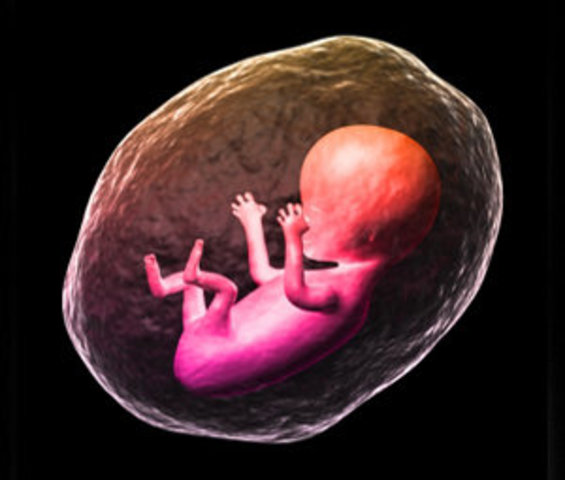

Segundo mes

El bebé ha crecido de forma espectacular dentro del útero materno en la semana 8 de embarazo. A partir de esta semana, deja de ser considerado un embrión para considerarse un feto.